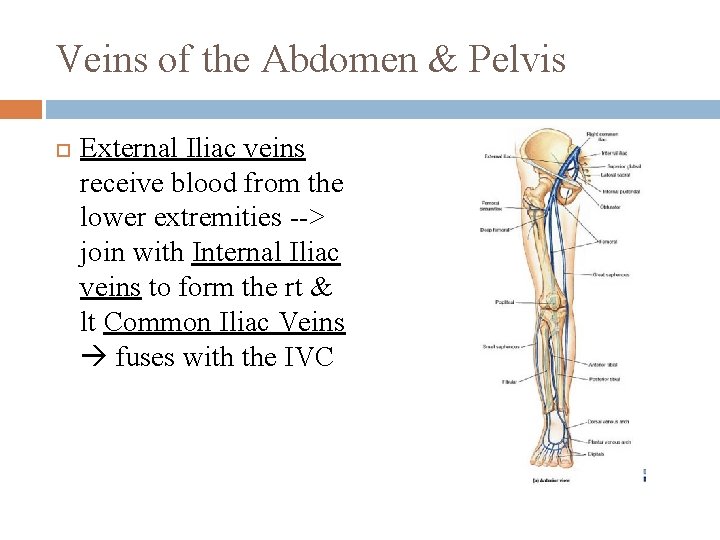

Veins of the Abdomen & Pelvis External Iliac veins receive blood from the lower extremities --> join with Internal Iliac veins to form the rt & lt Common Iliac Veins fuses with the IVC